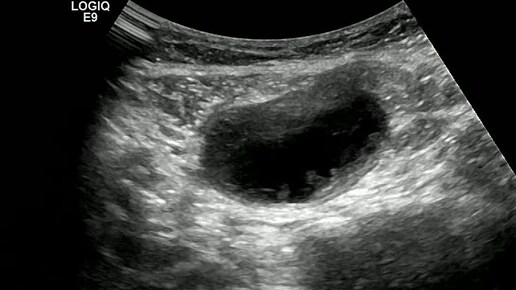

Видео к статье "Спонтанный разрыв прямой мышцы живота"https://dzen.ru/a/Z7_9JqiwzFHmuL7x

Ультразвуковые находки от врача УЗД Зорина Я.П.